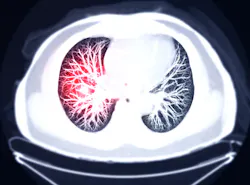

Diagnosing early-stage lung cancer with low-dose computed tomography (CT) screening drastically improves the survival rate of cancer patients over a 20-year period, according to a large-scale international study presented by Mount Sinai researchers at the annual meeting of the Radiological Society of North America.

The results show that patients diagnosed with lung cancer at an early stage via CT screening have a 20-year survival rate of 80 percent. The average five-year survival rate for all lung cancer patients is 18.6 percent because only 16 percent of lung cancers are diagnosed at an early stage. More than half of people with lung cancer die within one year of being diagnosed, making it the leading cause of cancer deaths. By the time symptoms appear, it is often too late.

The study tracked the 20-year survival rate of 1,285 patients who were screened in the International Early Lung Cancer Action Program (I-ELCAP) and who were later diagnosed with early-stage lung cancer. While the overall survival of the participants was 80 percent, the survival rate for the 139 participants with nonsolid cancerous lung nodules and the 155 participants with nodules that had a partly solid consistency was 100 percent. For the 991 participants with solid nodules, the survival rate was 73 percent. For participants with Stage 1A cancers that measured 10 mm or less, the 20-year survival rate was 92 percent.